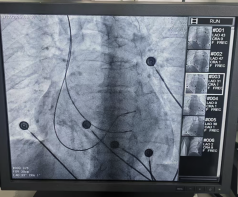

术中发现患者右房明显增大,下腔静脉增宽,三尖瓣重度返流,导致电极植入困难,在团队和导管室医技人员的密切配合下,先后植入两根主动起搏电极置于右室间隔。经过测试电极各项参数良好,CCM工作发送正常,患者各项生命体征平稳,手术全程仅40min左右。术后检查显示设备运行良好,患者生命体征平稳。